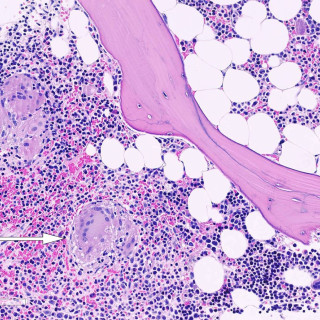

Magesmerter hos barn er en hyppig årsak til henvisning til barnemedisinsk og kirurgisk spesialisthelsetjeneste. Akutt appendisitt, obstipasjon og gastroøsofageal refluks er blant de vanligste diagnosene. Ofte kan barn ha diffuse symptomer, og selv om «det vanligste er det vanligste», er det viktig å være oppmerksom på symptomer som tyder på alvorlig, underliggende patologi. Tett samarbeid mellom fastlege, barnelege, barnekirurg og radiolog kan være viktig for å komme til målet. En jente tidlig i tenårene hadde vært plaget av «treg mage» siden småbarnsalder og hadde gjennom de siste fem årene...